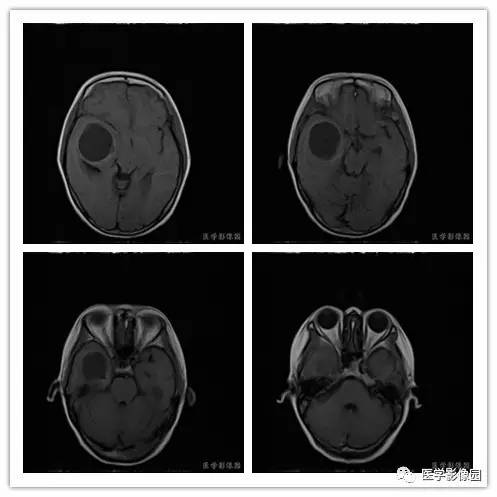

临床资料:女,59岁,于3月前无明显诱因出现左侧肢体乏力、记忆力下降,未行特殊处理,上述症状逐渐加重,并出现左侧面瘫。

影像学表现:右侧颞叶深部区见一长T1、长T2囊样信号,成明显环形强化、未见明确结节影,没有FLAIR和DWI图,内见分隔,边界较清,周围水肿不明显,右侧脑室明显受压、颞角扩大,右侧脑沟明显变浅,脑中线结果向左偏移。

结果 血管外皮细胞瘤